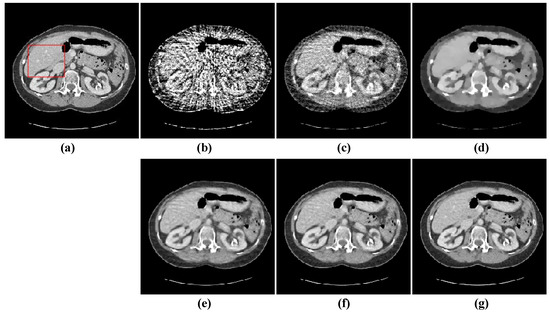

The second image reconstruction experiment is conducted on an abdomen image with more image details to show the feasibility of our algorithm for SVCT reconstruction, as shown in Figure 9. We extracted 80, 64, and 48 views from a full scan and set the parameters as follows: a = 0.5, γ1 = 0.1, and γ2 = 0.06. The reconstructed results using different algorithms are shown in Figure 10, Figure 11 and Figure 12. As can be seen from the figures, our algorithm performs better than other algorithms in preserving small structures and reducing noise. Specifically, FBP reconstruction results contain severe artifacts as displayed in Figure 10b, Figure 11b and Figure 12b. OS-SART reconstruction results also have obvious noise as displayed in Figure 10c, Figure 11c and Figure 12c. TV has a better performance than FBP and OS-SART, but the result has blocky artifacts, as displayed in Figure 10d, Figure 11d and Figure 12d. The PICCS and TVPI-G algorithms have an improvement in image quality, but fine image structures are losing detail and some edge information is blurring, as displayed in Figure 10e,f, Figure 11e,f and Figure 12e,f. As can be observed from Figure 10g, Figure 11g and Figure 12g, the proposed algorithm performs better not only in preserving edge and image details, but also in reducing noise.

Figure 10. 48-views reconstruction results of abdomen image: (a) ground truth, (b) FBP, (c) OS-SART, (d) TV, (e) PICCS, (f) TVPI-G, and (g) NPICCS. The display window is [−150 250] HU.

Applsci 13 10320 g010